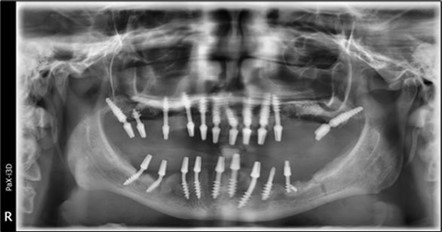

A total of 11 implants is placed in the maxilla, including compressive TPG implants with a polished surface in the maxillary-sphenoid fusion area (Figure 3, Figure 9). Similarly, in the anterior region, final fixation is achieved in the nasal cortex, and BCS corticobasal implants are added in areas with massive bone loss in the frontal region (Figure 3, Figure 8, Figure 11). Additionally, in the palatal sinus cortical area, with the aim of avoiding the addition and sinus lift zone where the second cortical bone no longer exists, 3 implants are placed, 2 in quadrant 1 and 1 in quadrant 2 (Figure 3, Figure 8). Through the Caldwell-Luc sinus lift procedure, the sinus cortical bone is displaced to allow the placement of the graft material and elevation of the sinus membrane. This sinus cortical is no longer recreated at the junction of the graft material and mucosa-sinus membrane, making it impossible to place a corticobasal implant, which relies on the second cortical bone. In the distal mandibular area, after the removal of two stage implants due to massive destruction in quadrant 3, implant placement distal to the mylohyoid line is not possible, as in quadrant 4 (Figure 10). A re-intervention occurs after 5 months to stabilize the area (Figure 12, Figure 14). Also, at the moment of fixation, the tip of one implant fractures, and the decision is made to leave it in place due to regional bone destruction, in order to avoid enlarging the bone defect.

In the interforaminal area (Figure 3, Figure 13), 6 corticobasal implants are also placed. The increased number of implants is due to the poorly represented distal area that needs to be compensated.

Figure 3.Panoramic pictures after removal of implants affected by peri-implantitis, extractions, alveolar crest regularization, and insertion of corticobasal and TPG implants (07.2022)

Panoramic pictures after removal of implants affected by peri-implantitis, extractions, alveolar crest regularization, and insertion of corticobasal and TPG implants (07.2022)

Figure 14.Rx panoramic final situation control: (a) Panoramic X-ray with the addition of a distal BCS implant in quadrant 3 at 11.2022; (b) Control X-ray, 10.2023.

Rx panoramic final situation control: (a) Panoramic X-ray with the addition of a distal BCS implant in quadrant 3 at 11.2022; (b) Control X-ray, 10.2023.

Figure 15.Follow-up panoramic X-ray 09.2025

Follow-up panoramic X-ray 09.2025

The results of rehabilitation treatment with corticobasal and compressive implants with a polished surface after the failure of two stage implants were highlighted over a period of 3 years and 3 months as being very good (Figure 14, Figure 15), with the patient completing a satisfaction survey in this regard. Certainly, it is necessary to continuemonitoring these results in the long term.